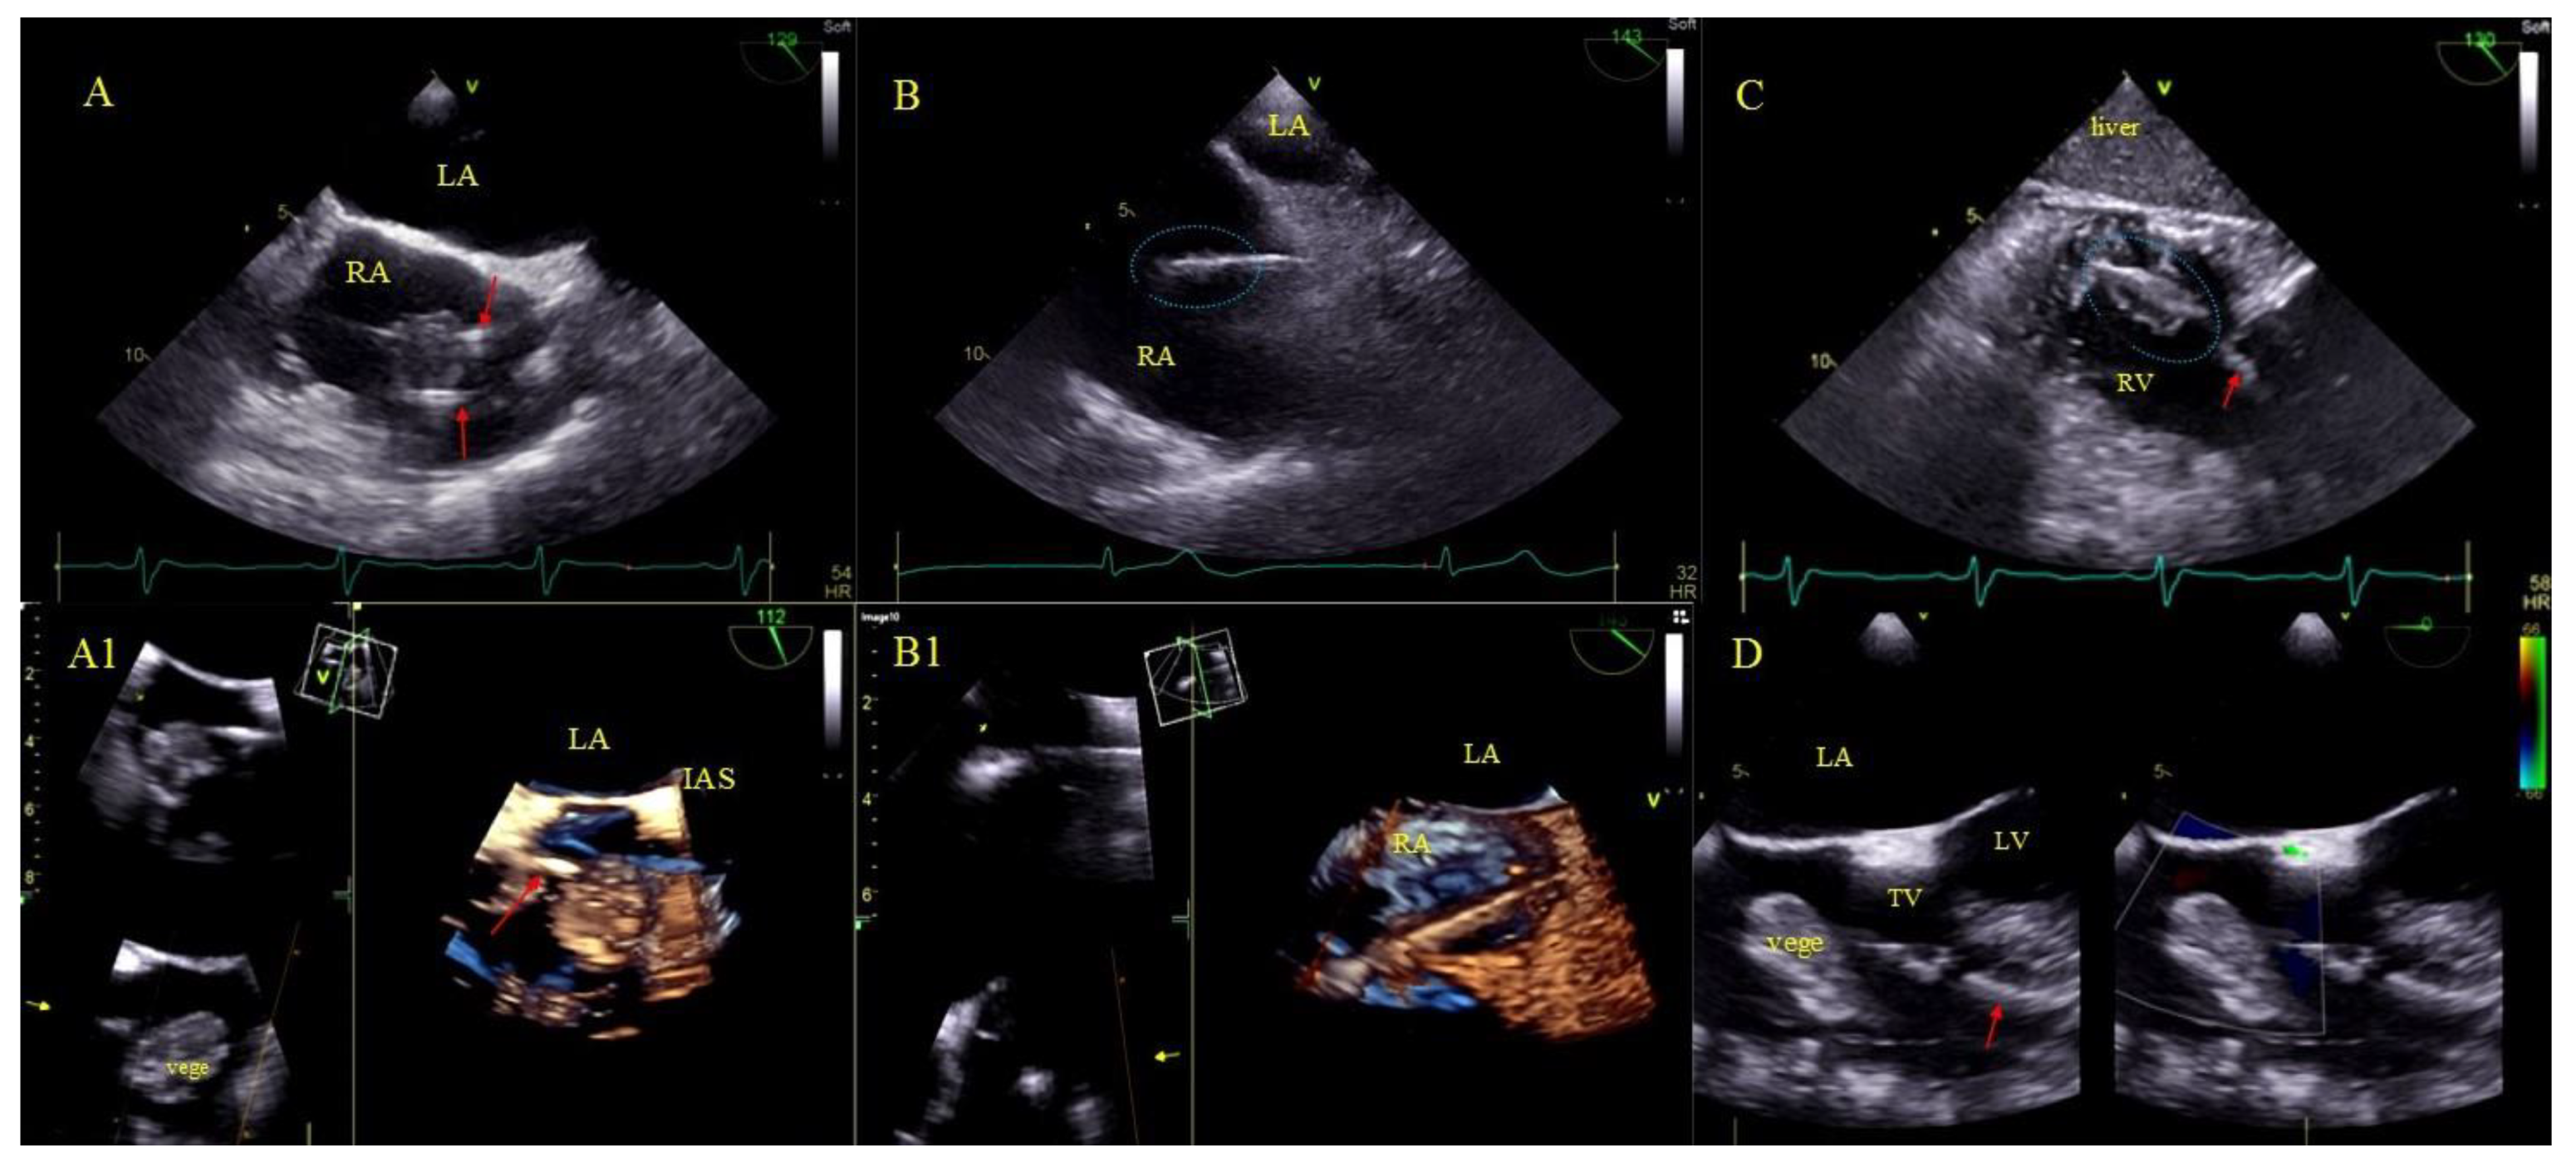

2.5. Echocardiographic Findings Associated with Endocardial Leads: Definition and Classification According to the Anatomy and Characteristic Features

- Non-modifiable factors related to the underlying disease (indication-dependent):Vegetations and LRIE have always been (in all previous analyses, including ours) one of the most potent factors decreasing chances of long-term survival [5,6,7,8,9,10,11,12,13,14,15,16,17,18,19,20,21,22]. Unfortunately, despite the improving standards [2,3,4] long-term mortality among patients after TLE performed due to LRIE does not improve as desired.